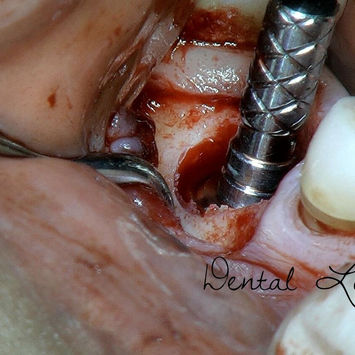

Incision made over #46 region.

Buccal and lingual flaps raised.

Failed implant at #46 trephined and removed in total.

Implant bed prepared with implant drills and osteotomes.

Dentium Superline 7.0 mm × 8.0 mm implant placed.

Dentium Healing Abutment 7.5 (M) inserted.

Bone grafting performed using 1.0 cc EthOss artificial graft material.

Flap released; BSS × 07 placed for primary closure.

Hemostasis achieved; post-operative instructions given.

Photographs taken.